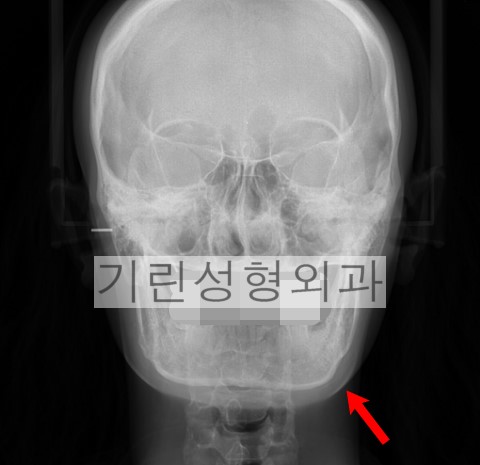

*귀뒤사각턱 후 개선되지 않은 얼굴형. 여전히 넓은 U라인.

사각턱수술에는 여러가지 방법이 있습니다. 귀뒤사각턱수술은 입안절개를 하지 않기 때문에 부기가 적어 일상생활로의 복귀가 빠른 장점이 있습니다.

하지만 현재까지 제가 알고있는 수술방법 중 귀뒤사각턱 수술을 통해 정면에서 갸름보이도록 하는 방법은 없습니다. 분명 귀밑각을 제거하는데 왜 갸름한효과가 없을까요.

이 수술은 말 그대로 귀뒤 절개창을 통해 단순히 귀밑각의 제거만 이뤄지기 때문에 앞턱에 어떤 조작도 가해지지 않습니다. 귀밑각만 제거할 경우에는 앞턱이 갸름하거나 전체적으로 브이라인에 가까운 사람에 한해 효과가 있다는 전제가 붙어야 합니다. 이러한 전제조건이 붙는다면 분명 효과적이고 환자입장에서 이득이 큰 수술이지만 대부분 수술을 고민하는 사람들은 그렇지 않다는 것이 문제입니다.

재수술로 내원하시는 환자분 중 많은 비중을 차지하는 원인이 효과미비이며 사각턱수술을 받았지만 정면에서 볼때 전혀 얼굴형이 개선된 느낌을 받지못했다는 것이 바로 그 이유입니다. 덧붙여 부작용의 또 다른 원인으로는 이차각이나 비대칭인데 재수술 시 가장 까다로운 것이 뼈의 과절제로 그런경우 뼈이식을 고려해볼 수 있겠습니다.

*빨간화살표: 절골된 범위. 노란화살표: V라인효과를 위해서 절골되어야 하는 범위.

위 엑스레이사진을 통해 정면효과가 없는 이유에 대해서 말씀드리겠습니다. 사례에서 귀밑각이 잘려나간 범위는 붉은화살표까지로 앞턱의 개선이 없어 당연히 정면효과 및 브이라인효과가 떨어질 수 밖에 없는 것입니다. 수술은 반드시 노란색화살표까지 절골되거나 앞턱수술이 병행되어야 만족할만한 예후를 기대할 수 있습니다.